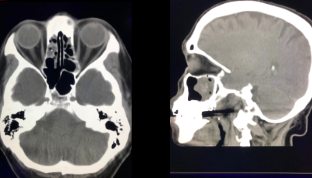

Q

¿Qué se ve en esta imagen?

A

Sinusitis + Mucocele